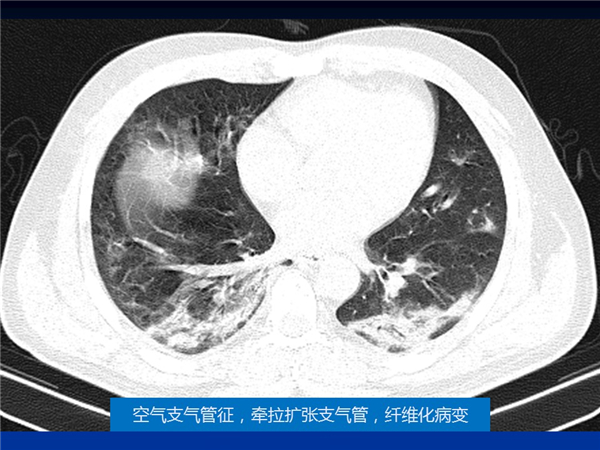

【病例分享】新型冠狀病毒感染肺部CT影像4例(常德市第一人民醫(yī)院)